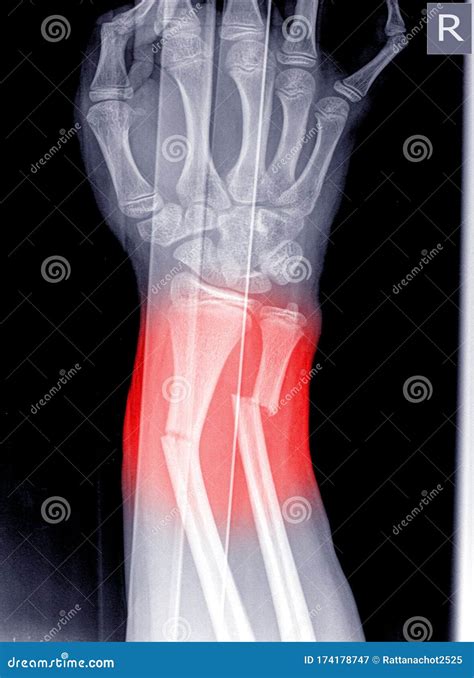

• X-rays: X-rays are the primary imaging tool used to confirm the presence and type of fracture. They provide detailed images of the bones and can help determine the severity of the injury.

• Surgery: In severe cases, surgery may be required to realign the bones and stabilize the fracture with plates, screws, or pins.

Metacarpal Fractures Fractures in the metacarpal bones, which connect the fingers to the wrist. Punching a hard surface, falls, or direct blows.